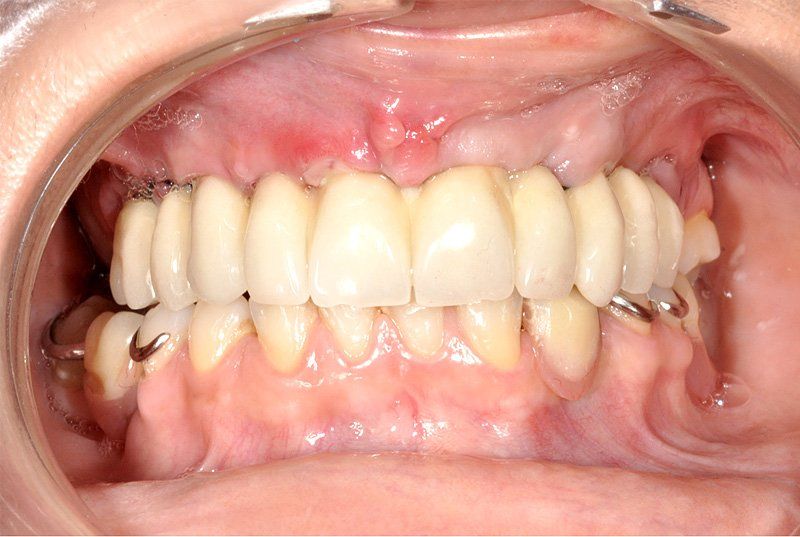

Sus beneficios son que se instalan con mayor tranquilidad para usarlos, no hay que sacárselo todas las noches, la gente queda con una mayor seguridad interna, mejora la autoestima, el humor y las relaciones interpersonales.

Porque se hace en pabellones certificados por la Universidad de Chile. Son dependencias hechas única y exclusivamente para hacer intervención en sitios estériles. También se hace más cómodo y se pasa rápido el periodo de espera. Del momento en que se insertan los implantes debe transcurrir un período de tiempo de entre 4 a 6 meses si es en mandíbula o maxilar superiores respectivamente para que el tejido óseo cicatrice y logre integrarse a la superficie del implante